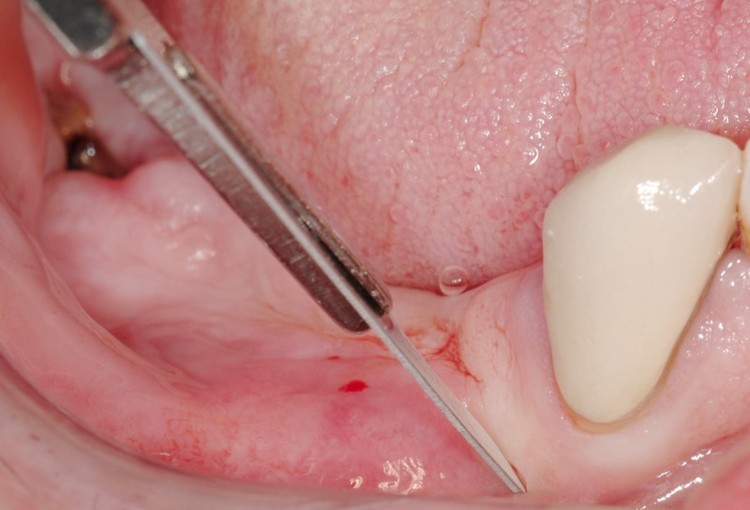

3. 微創植牙技術

疼痛程度低,傷口小且快速的植牙技術。

我们使用PRF技术来治疗包括拔牙,植牙,加骨粉等相关手术。纤维蛋白补骨技术(Platelet Rich Fibrin)由自体的血液抽取少量经离心萃取,这样可以避免因<人工化学合成生长因子>发生的感染问题及<非自体组织排斥效应>.由于纤维蛋白兴血小板会形成凝块,具有立即止血效果。植牙者如果牙槽骨缺失搭配骨粉可增进成骨细胞附着生长及加速伤口愈合,是一种非常安全却有效的疗程!需要治疗牙周病,牙龈再生,拔智齿,加骨粉,植牙等可以随时打电话或者访问牙科咨询。纽约综合牙科诊所 Dr.Jason Kim 是纽约大学学院的临床助理教授,也是该大学牙科种植学继续教育项目的外科主任。Dr.kim 持有23年的植牙经验,擅长植牙,牙槽骨重建,牙周治疗等专业牙科技术。